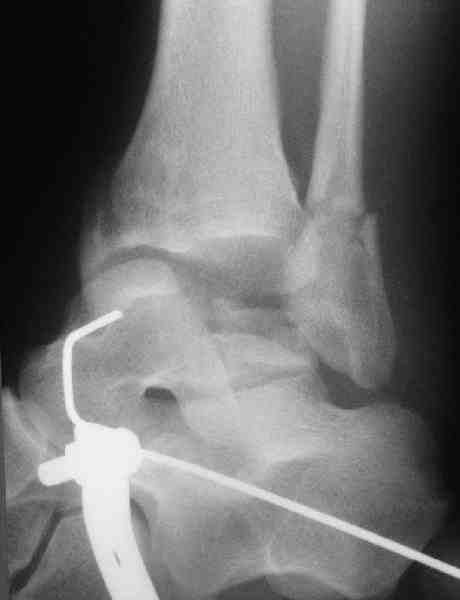

повторили рентгенограммы и доделали проекции, к единому мнению все еще не пришли

На ренгенограмме не уловил многоскольчатость тарана, чтобы доказать, конечно, можно было исследовать на КТ, потом КТ дает ориентацию фрагментов.

Два фрагмента суставной поверхности тарана можно восстановить боковой компрессией шурупами и дополнительно костная пластика.

Наружный фиксатор "голень-пятка", "лигаментотаксис" при поступлении, домой через 48 часов после обучения ходьбы на костылях, в течение ближайшего времени осмотр в поликлинике для определения кондиции мягких ткани (тест на образование морщин в зоне разреза), при отсутствии отека примерно на 6-7 день с момента травмы операция.